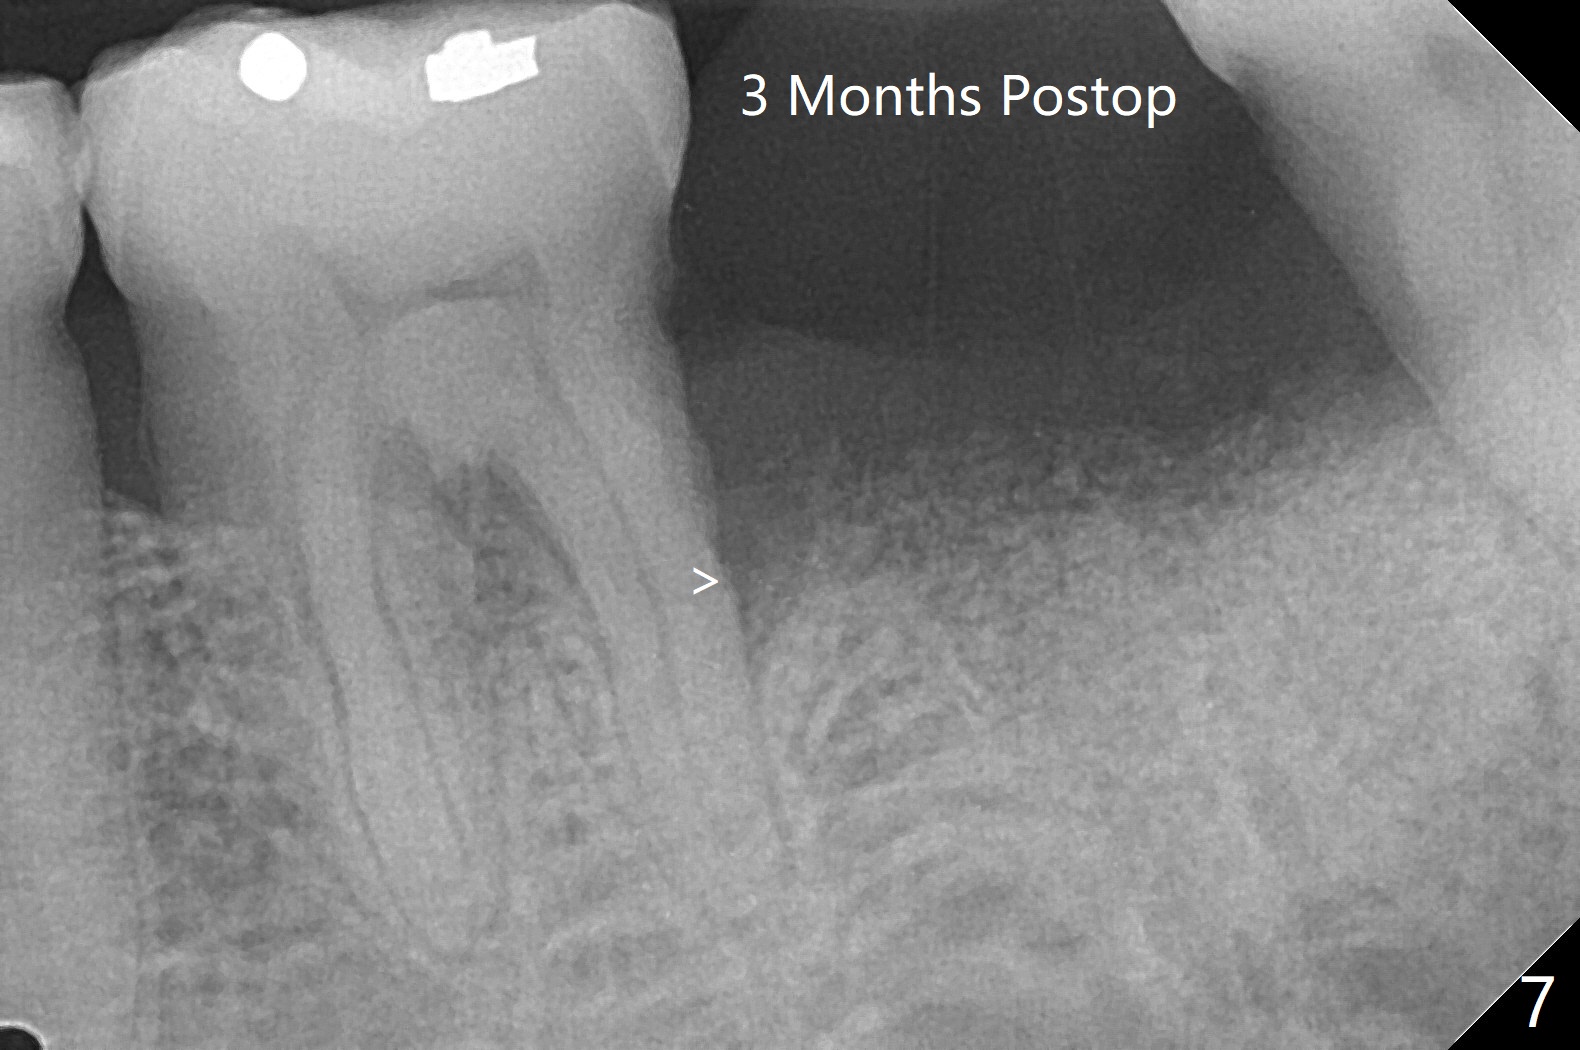

60岁男,吸烟,口腔卫生不好,不积极配合治疗,下前牙两个植体螺纹暴露,但是没有症状。两年中,左下七(图一,二)不能保留(图三),虽然六远中结石被清除(图三>),七位点保留(图四 *)时未能顺便在六远中填入骨粉(用血混合,胎盘膜覆盖)。四五个月后,七种植时将钻头骨粉放置于六远中缺损处,如何才能让骨粉在患处生根发芽?术后一个月,去除树脂敷料后,最表面骨粉未能被整合,下面骨粉好像已经与肉芽组织结合了(图五),其实根尖片应该拍摄证实这一点。吸烟者血供不好,愈合欠佳。术后三个月牙槽嵴宽(图六);高度稍微减低(图七)。术后4个月CT显示近中牙槽窝正好位于缺牙区正中(图八),所以植体必然进入近中窝(图九)。